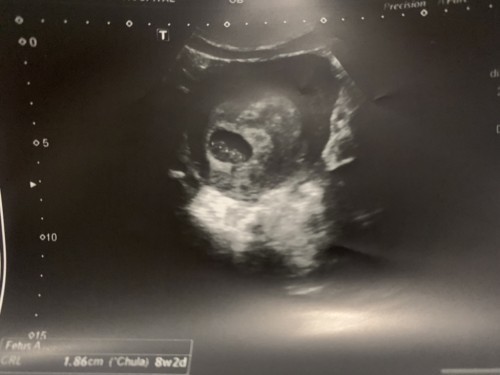

เป็นท้องที่ตั้งใจจะมี ปล่อยมาปีกว่าๆแต่ก็ไม่เคยมาปรึกษาหรือตรวจสุขภาพ จนตอนนี้มีน้องอย่างที่อยากมีแล้ว แต่น้องมาพร้อมกับเราเป็นซีสต์ที่รังไข่ข้างขวา หัวใจเต้นผิดปกติจากที่หายไปแล้ว 6ปี และวันนี้ตรวจเจอไทรอยด์ กับพาหะธาลัสซีเมีย ต้องรอผลตรวจคุณพ่อแล้วตอนนี้ ภาวนาเลยอย่าให้พ่อเป็นพาหะอีกคน ไม่งั้นหนูไม่แข็งแรงแน่ๆ แม่จะพยายามบำรุงให้หนูแข็งแรงตอนเกิดมานะ วันนี้อัลตราซาวน์เจอตัวหนูกับหัวใจดวงน้อยๆเต้น แม่ดีใจมากๆเลย #ใครมีประสบการณ์ #ท้องแรก